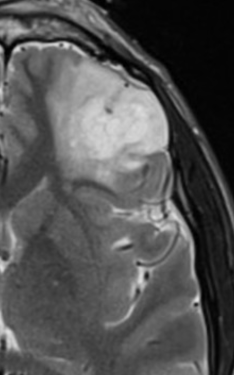

Glioblastome

Decouverte fortuite aux urgences, Confirmé a la patho

Decouverte fortuite aux urgences, Confirmé a la patho